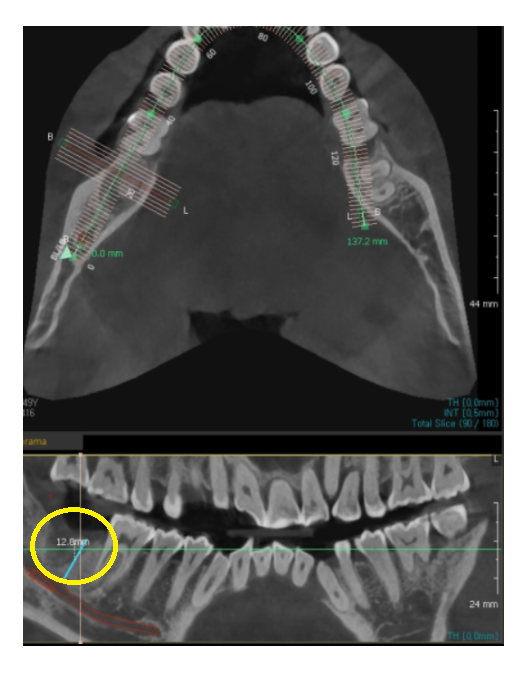

ct 상에서 잇몸 뼈 한쪽이

움푹 패여졌네요.

잇몸 뼈 깊이를 재어보니 12.8mm 정도 나왔습니다.

임플란트 길이는 어금니의 경우 8-10mm정도 심으니까

충분합니다.